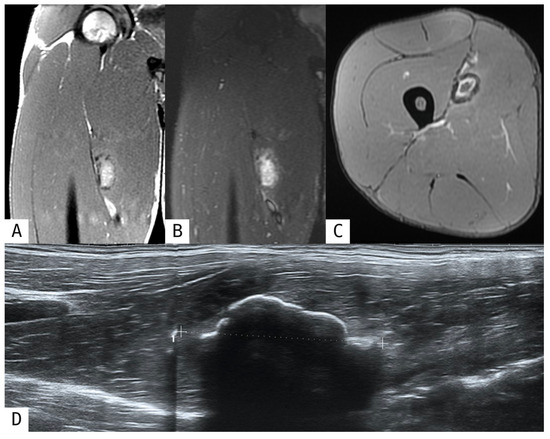

Revisiting Myositis Ossificans: A Comprehensive Stage-by-Stage Imaging Review

by Consolato Gullì, Giuseppe Ferrara, Emanuele Ferravante, Roberto Calbi, Mario Di Diego, Davide Parisi, Daniele Perla, Tommaso Villa and Luigi Natale

Muscles 2026, 5(2), 27; https://doi.org/10.3390/muscles5020027 - 14 Apr 2026

Myositis ossificans (MO) is a benign, self-limiting heterotopic ossification process that typically develops within soft tissues following trauma, although non-traumatic forms have also been described. Despite its benign nature, MO frequently represents a diagnostic challenge, particularly in its early stages when imaging findings [...] Read more.

Myositis ossificans (MO) is a benign, self-limiting heterotopic ossification process that typically develops within soft tissues following trauma, although non-traumatic forms have also been described. Despite its benign nature, MO frequently represents a diagnostic challenge, particularly in its early stages when imaging findings may mimic aggressive soft-tissue tumors, leading to unnecessary biopsies or surgical interventions. This narrative review provides an updated overview of the classification, pathophysiology, and imaging features of myositis ossificans, with a specific focus on the time-dependent evolution of radiologic appearances across different imaging modalities. Radiologic findings are discussed according to disease stage, highlighting key diagnostic clues such as the zonal phenomenon and peripheral maturation pattern. In addition, the main entities included in the differential diagnosis are reviewed, with particular emphasis on imaging features that help distinguish myositis ossificans from soft-tissue sarcomas and other calcified or ossified lesions. Finally, current management strategies and the role of imaging in patient follow-up are summarized. A thorough understanding of the evolving imaging spectrum of myositis ossificans is essential for radiologists and clinicians to achieve an accurate diagnosis, guide appropriate management, and avoid overtreatment. Full article

Show Figures

Figure 1